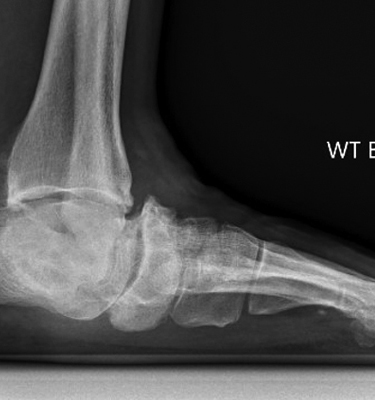

The ankle joint connects the leg to the foot and comprises three bones: the tibia, fibula, and talus. The tibia (shinbone) and fibula (calf bone) are the bones of the lower leg that articulate with the talus (ankle bone), enabling up-and-down movement of the foot. The joint surfaces of all these bones are lined by a thin, tough, flexible, and slippery surface called the articular cartilage, which acts as a shock absorber to cushion and reduce friction between the bones. The cartilage is lubricated by synovial fluid, which further enables smooth movement of the bones. Ligaments are tough, rope-like bands that connect bones to other bones, holding them in place to provide joint stability.

Ankle fusion surgery may be performed as an open surgery, where a large incision is made, or as a minimally invasive arthroscopic surgery, where small incisions are made to insert an arthroscope (a thin tube with a camera and light source) and miniature surgical tools. Open surgery is the commonly employed approach and involves the following steps:

- The joints are then fused together with the help of screws, wires, plates, or rods.